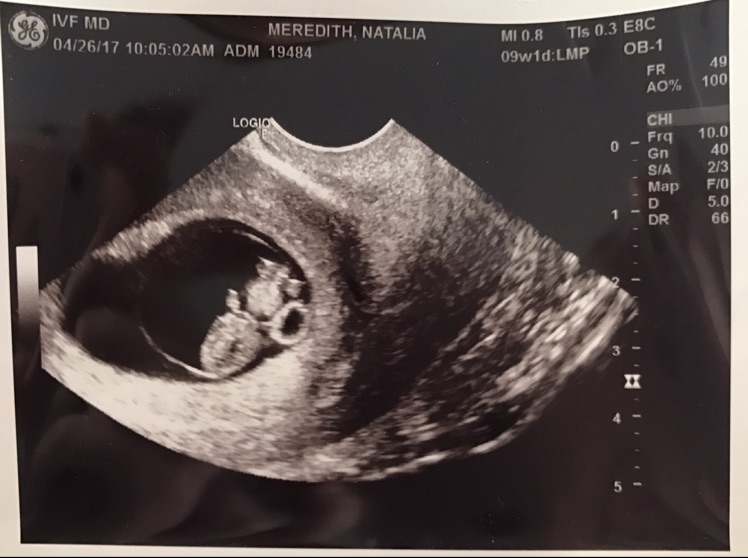

5. エコー写真と妊娠週数の関係

出生前診断を検討する時期は、初めて赤ちゃんのエコー写真をもらう時期と重なります。「妊娠8週のエコー写真」は、赤ちゃんの心拍がしっかり確認でき、手足の芽が見え始める感動的な時期です。

📸 妊娠週数別エコー写真の見え方

-

•

妊娠5~6週:胎嚢(赤ちゃんの部屋)が見えます。まだ赤ちゃん自身は見えないことが多いです。

妊娠7~8週:【検査検討のタイミング】心拍が確認され、「二頭身」の可愛い姿が見え始めます。この時期にNIPTなどの出生前診断について調べ始める方が最も多いです。

妊娠9~10週:人間らしい形になってきます。ミネルバクリニックでは、この9週0日から標準的なNIPT検査が可能です。